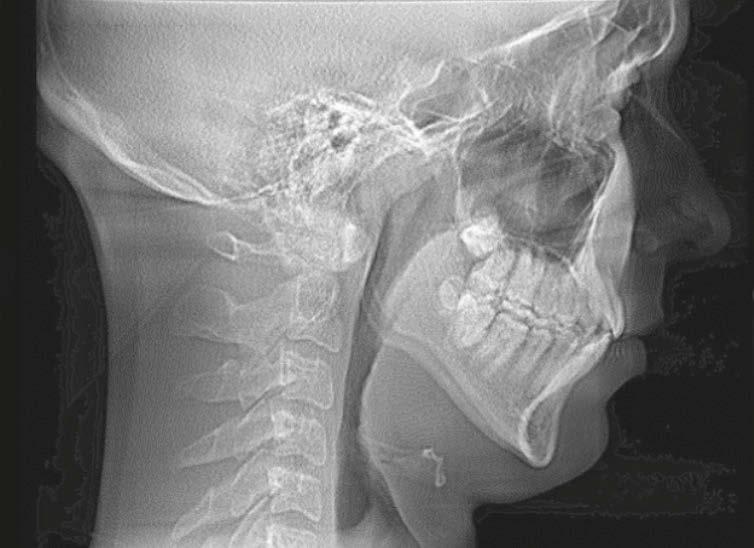

In children, screening through history and clinical examination may identify signs and symptoms of deficient growth and development, or other risk factors that may lead to airway issues. If risk for SRBD is determined, intervention through medical/dental referral or evidenced-based treatment may be appropriate to help treat the SRBD and/or develop an optimal physiologic airway and breathing pattern.

It is widely believed that current dental education does not prepare dentists to recognize pediatric airway issues.